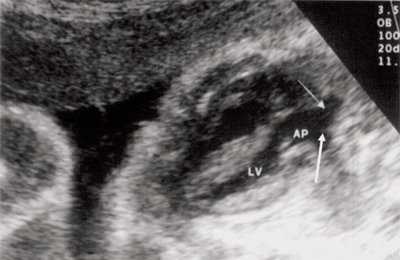

При эхокардиографии изучались четырехкамерный срез сердца плода (рис. 1) и срез через три сосуда (рис. 2). УЗИ проводилось трансабдоминальным датчиком, лишь при необходимости (затрудненная визуализация) использовался внутриполостной датчик. Четырехкамерный срез сердца плода при ультразвуковом сканировании трансабдоминальным датчиком визуализировался в 85% случаев, срез через сосуды - в 73%, при использовании трансвагинального датчика эти цифры существенно возрастали до 100 и 91% соответственно. Оптимизация пренатальной диагностики ВПС может быть достигнута путем строгого соблюдения основных методических правил. При оценке четырехкамерного среза плода необходимо оценить нормальное расположение сердца плода, исключив его эктопию (рис. 3), положение оси сердца плода, что не представляет никаких трудностей, нормальные пропорции и размеры камер сердца, движение створок атриовентрикулярных клапанов должно быть свободным, септальная створка трикуспидального клапана должна располагаться ближе к верхушке сердца (рис. 4). При оценке среза через три сосуда необходимо оценить взаиморасположение сосудов и их диаметр.

Рис. 1. Беременность 12 недель. Четырехкамерный срез сердца плода. Отчетливо видны камеры сердца.

Исходя из особенностей внутрисердечной гемодинамики плода, для диагностики коарктации аорты были предложены косвенные признаки патологии в антенатальном периоде: дилатация правого желудочка и его гипертрофия (см. рис. 3), дилатация легочной артерии [6, 7, 14]. Авторы считают, что это достоверные признаки и встречаются они достаточно часто (в 18 из 24 случаев верифицированных диагнозов коарктации аорты). Поэтому была предложена оценка индексов отношения полости правого желудочка к левому (в норме - 1,1) и легочной артерии к аорте (у здоровых - 1,2). Исходя из увеличения этих параметров, можно предположить наличие затрудненного выброса в аорту или гипоплазию дуги аорты. Тем не менее, по данным предложивших эти косвенные признаки авторов, такие изменения выявляются только в 30% наблюдений (рис. 4).

Рис. 4. Диспропорция размеров желудочков сердца при коарктации аорты. RV - правый желудочек; LV - левый желудочек; AO DESC - поперечное сечение нисходящего отдела аорты.